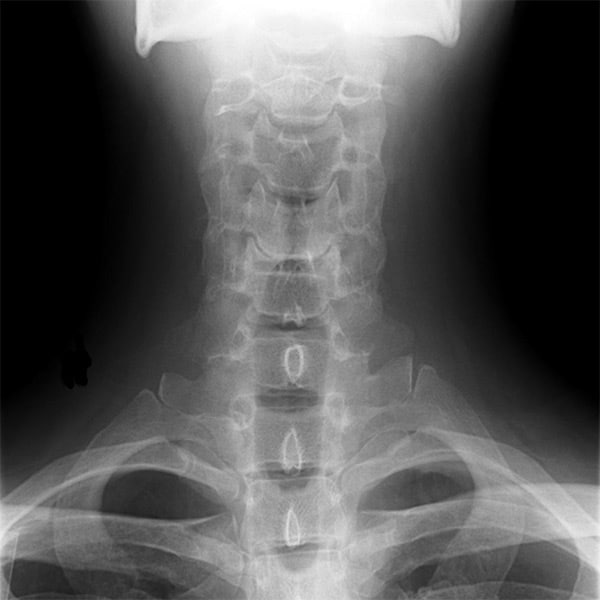

The research has particular potential for the repair of damaged cartilage and bone in joints and the spine – conditions that plague professional athletes and those who do a lot of manual labour as part of their jobs.